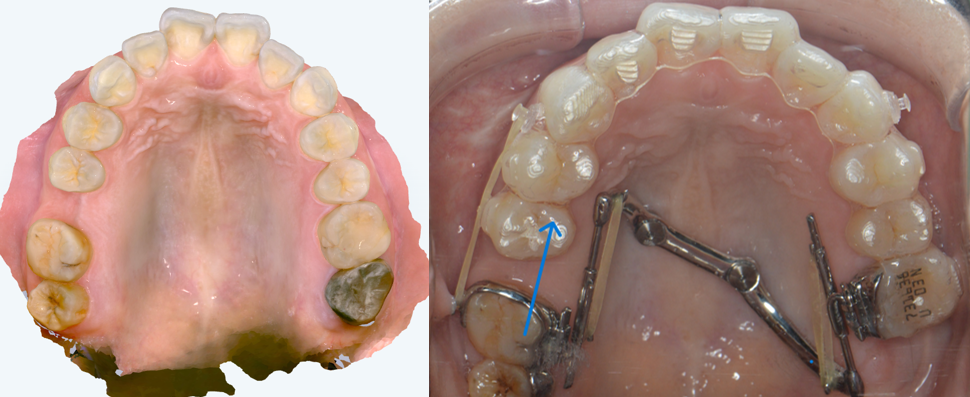

multi bracket

オーラルパワー

抜歯と非抜歯、どちらが正解?